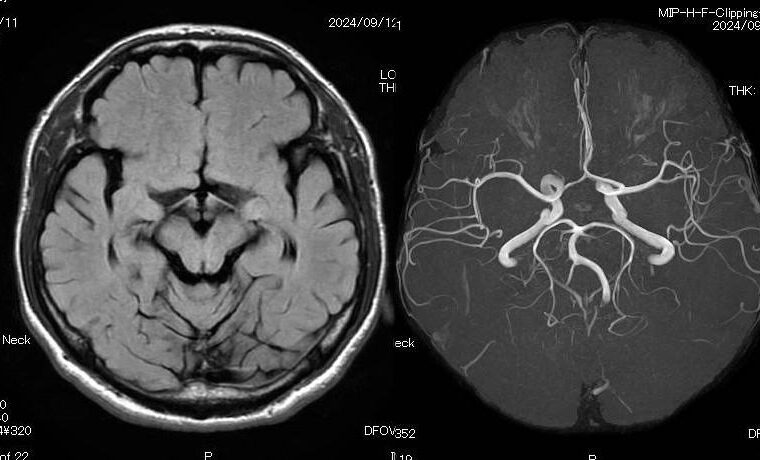

臨床検査室と内視鏡センターを持ち、MRIやマルチスライスCT、X線透視検査など先進の検査機器を備え、高精度な検査結果を迅速に提供

健康診断では血液検査やレントゲン検査が一般的ですが、近年はMRI(磁気共鳴画像)を用いた人間ドックも注目されています。MRIは強い磁場と電波を利用して...